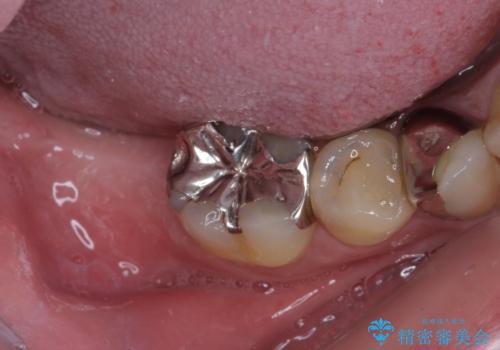

- 下顎左右の奥歯を治療途中で放置してしまっているとのことで来院された患者様です。

欠損部はインプラントによる補綴治療を、土台の外れてしまった歯は、根管治療を行った上で、補綴治療を行うこととしました。

骨格的に下顎が大きく上顎が小さいため、奥歯に力の負担のかかりやすい咬み合わせであるので、治療後は睡眠時にマウスピースを装着することで、セラミッククラウンやインプラント、治療をしたご自身の歯が長持ちするよう指導しています。